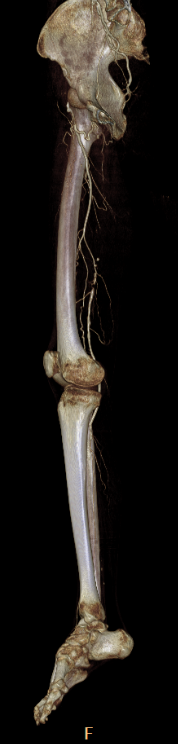

辅助检查:下肢动脉CTA提示:右髂外动脉、股动脉栓塞。

当地医院左侧髂动脉支架远端跨关节,至股浅动脉。

造影显示右侧髂外动脉、股动脉血栓栓塞。